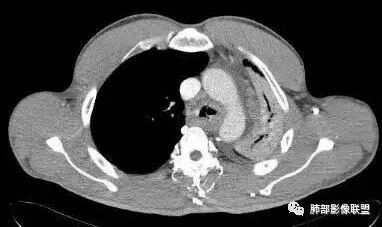

男,81,咳嗽、胸闷20天,咯血2天。胸部CT:左主支气管狭窄、管壁环形增厚,部分层面左主支气管壁高密度,骨化?左叶裂广泛不均匀增厚,结节感。3个月后左侧胸廓塌陷,左主支气管狭窄明显,左肺大部不张。考虑支气管TB并肺不张?支气管骨化?鉴别Ca、淀粉样变、复发性多软骨炎、GPA等

3/18:左主支气管壁弥漫增厚